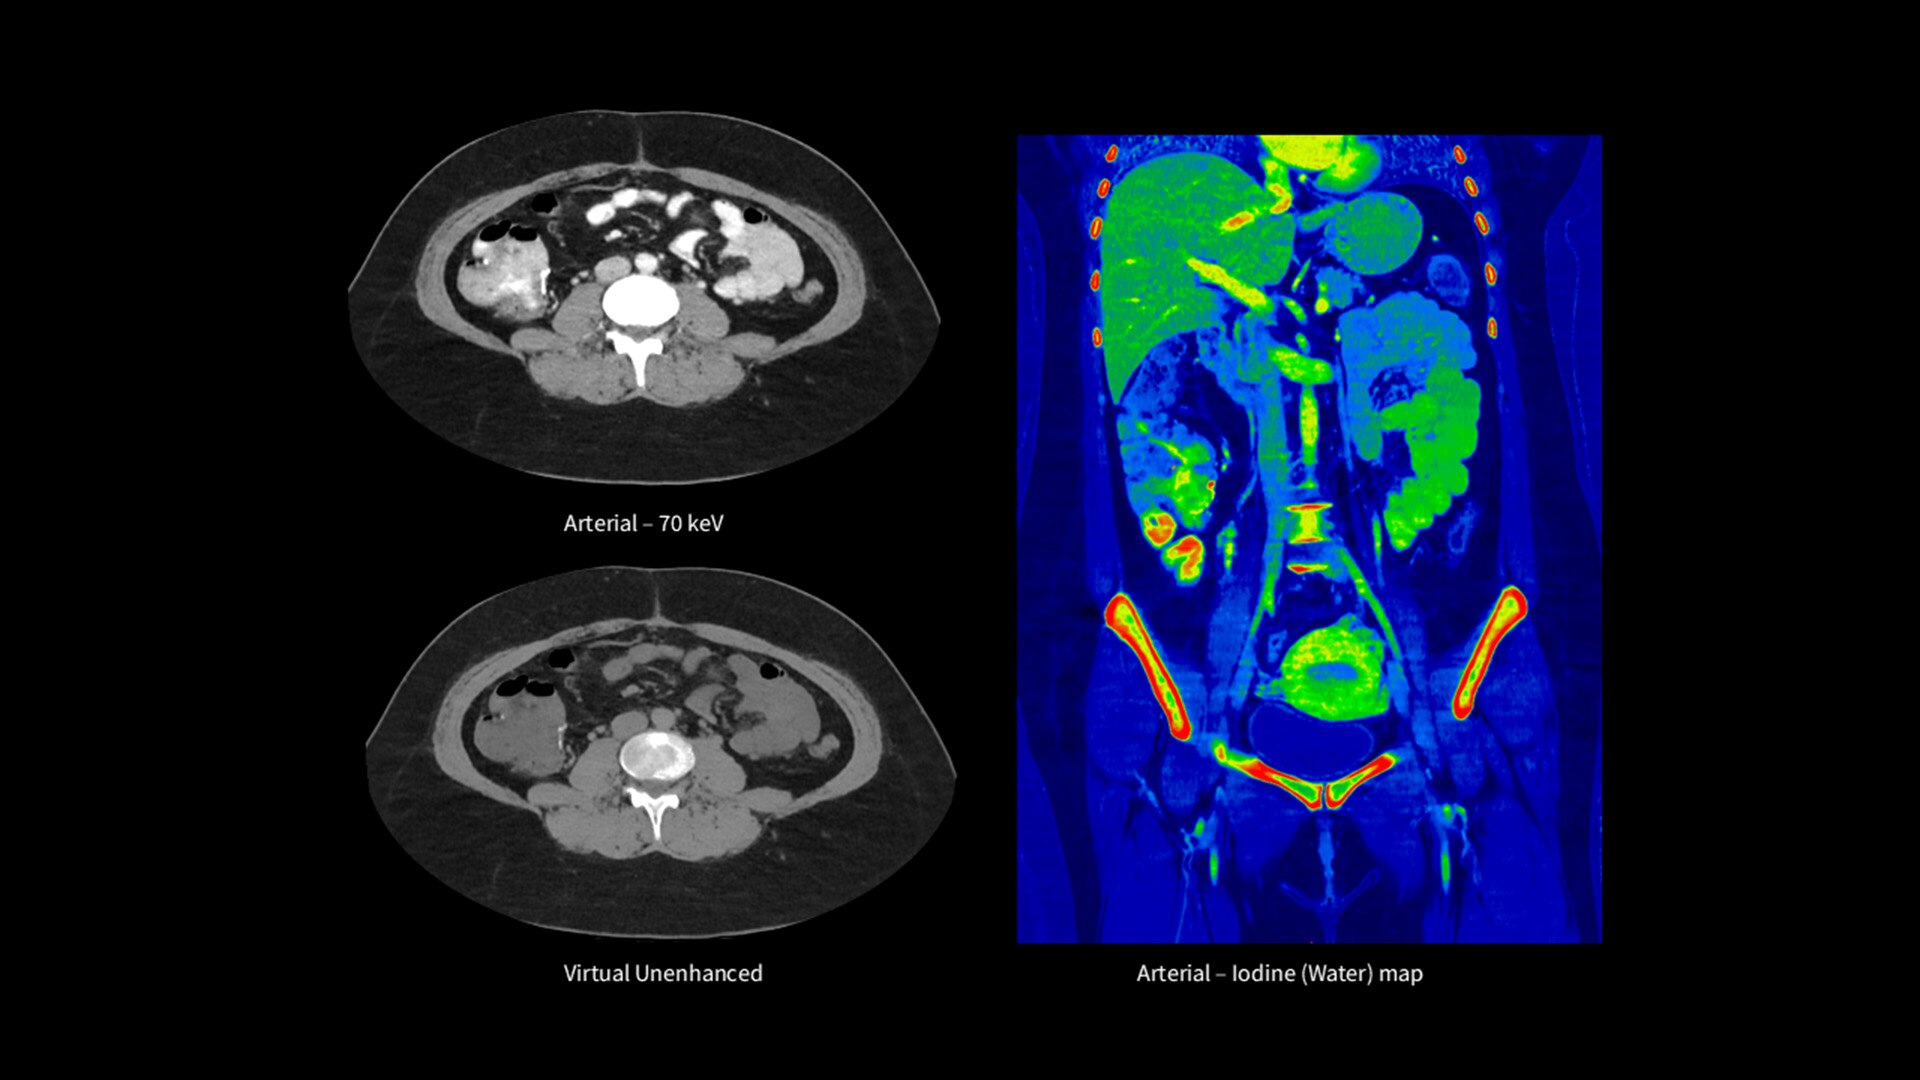

Unlimited 1-Beat Cardiac is designed to provide consistent, high-quality imaging for accurate diagnoses, even in challenging patients with atrial fibrillation, breath-holding difficulties, heavily calcified coronaries, in-stent restenosis, and situations where an ECG trace is unavailable.